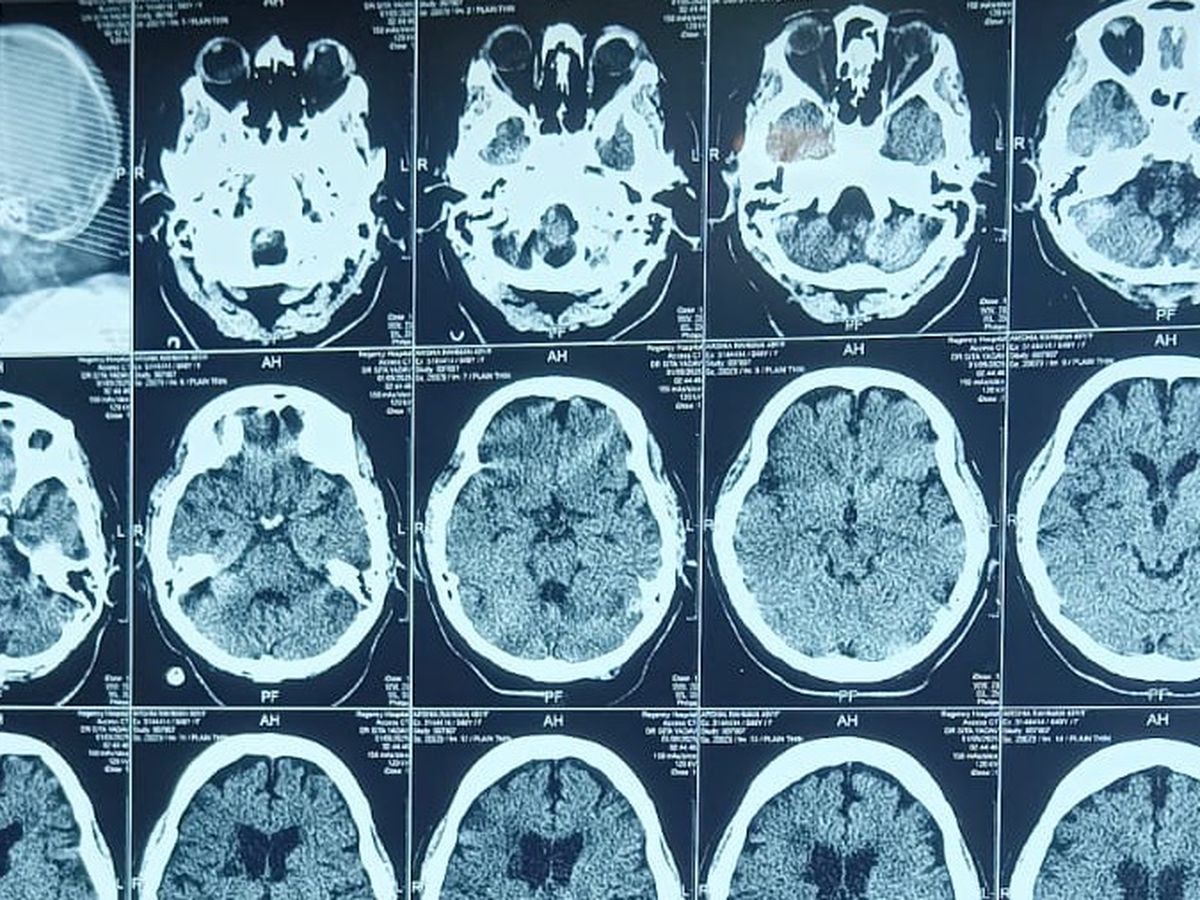

Just weeks ago, she suffered a catastrophic brain stroke, causing swelling in 90% of the right side of her brain and leaving her left side paralysed. On top of this, her heart is functioning at only 30-35%, and her kidneys have failed, requiring ongoing dialysis. She is currently in the ICU, fighting for her life, supported by ventilators and round-the-clock care.